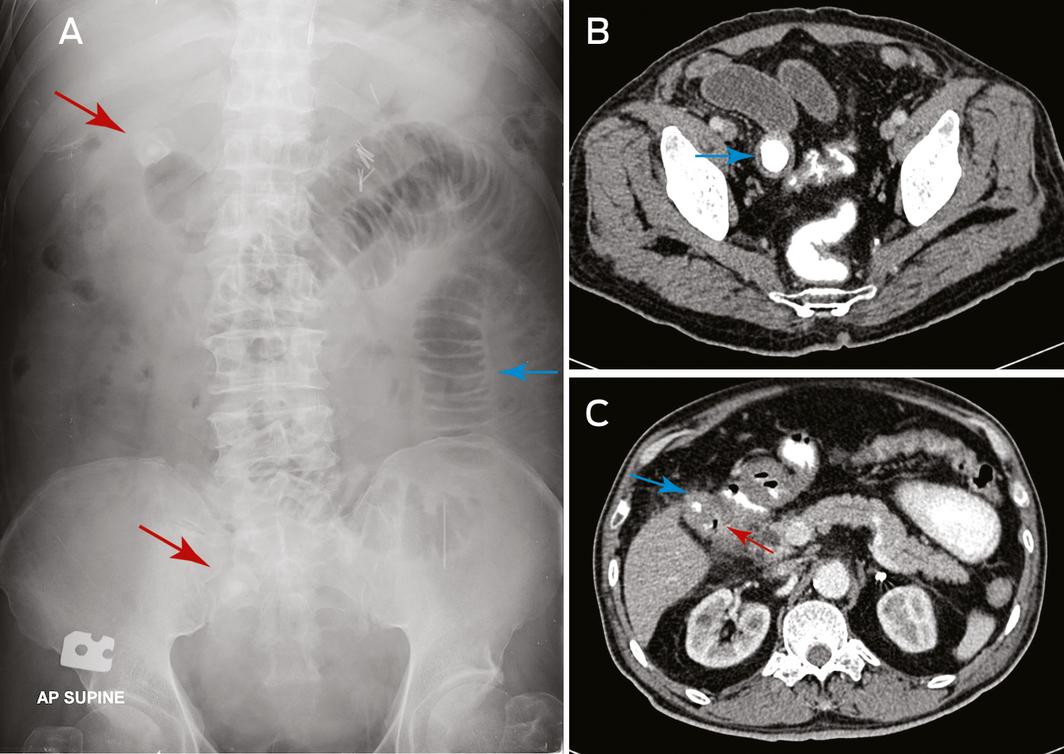

Gallstone ileus